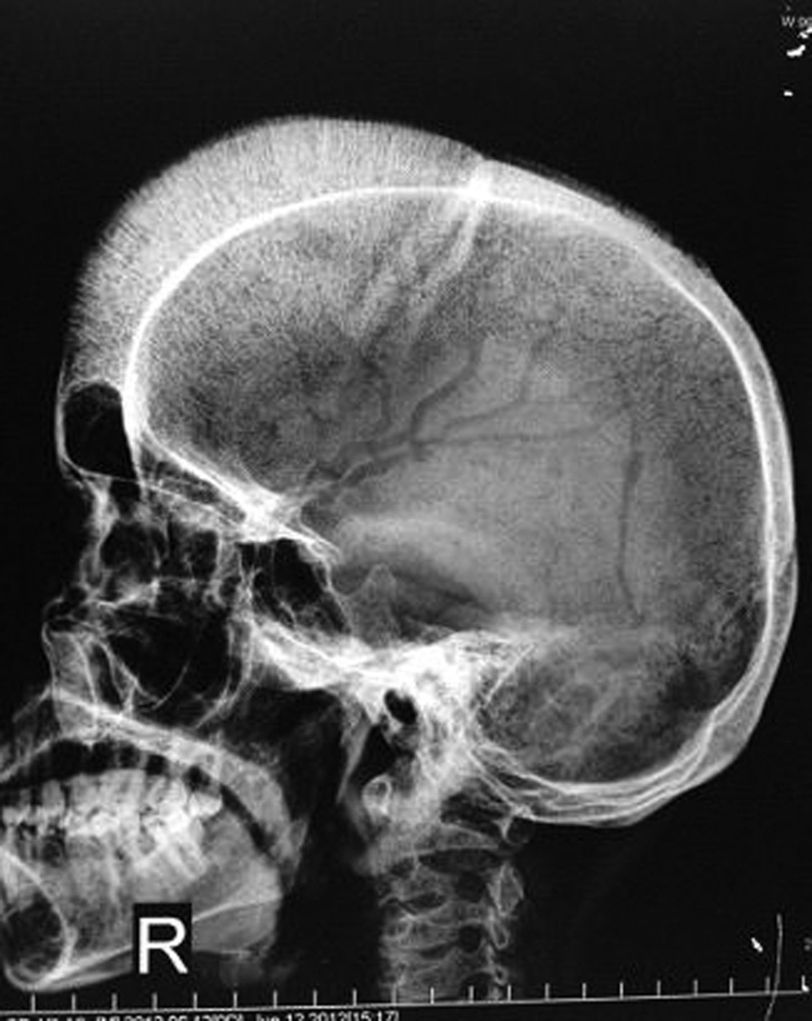

Chronic hemolysis.. Is the cause of such appearance.. Causes of chronic hemolysis are several.. But two most important are. 1. Thalassemia major. 2. Sickle cell anemia.

Excessive erythropoiesis is the cause for this kind of appearance. So the disease are those which increases the erythropoiesis & this happens in the diseases where there is greater hemolysis